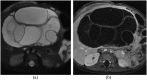

Hamartomas are tumours composed of mesenchymal tissues such as cartilage, fat, connective tissue and smooth muscle and can be found in virtually any organ system. These masses commonly develop sporadically, but are also seen in certain syndromes such as tuberous sclerosis or Carney triad. While their imaging appearance varies depending on the organ they arise from, findings are usually unique and a diagnosis can be confidently made. Radiologists must be aware of the clinical and imaging presentations of these lesions with the particular goal of avoiding unnecessary studies or invasive procedures. Furthermore, knowledge of common syndromic entities is crucial, as the radiologist may be the first to suggest the diagnosis.